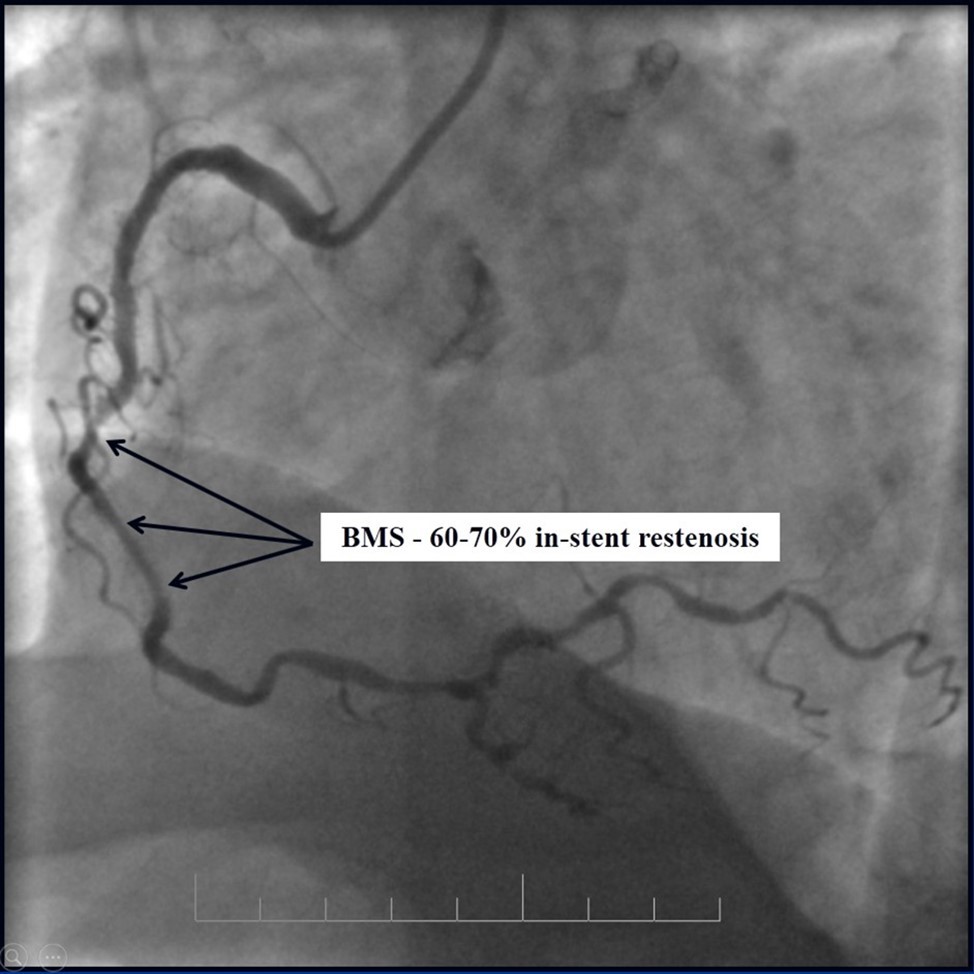

Due to financial problems the second stage was performed after 3 months (during this time the patient solved his financial problems). CAG revealed patent stents in LAD (Figure 7), and 60-70% restenosis by BMS in RCA (Figure 8). In-stent restenosis was treated by plain old balloon angioplasty (POBA), the optimal result was obtained (Figure 9). After LMCA quadrifurcation balloon predilation, 2.5×26 mm DES (Resolute Integrity, Medtronic) was implanted in the IMA, using a modified balloon mini-crush technique. The stent was minimally protruded in the LMCA and its edge was crushed by preloaded MB balloon. Next 2.5×30 mm DES (Resolute Integrity, Medtronic) was implanted in OM1 through the CX (first marginal and circumflex arteries in this particular case have the same ostium). The stent was protruded in the LMCA as in conventional modified balloon crush stenting technique, after stent deployment, its balloon was pulled back and overinflated, then protruded stent was crushed by preloaded MB balloon (Figure 10). 3.5×15 mm DES was implanted in the LMCA so that distal part of the stent covered ostial and proximal segments of the LAD. Sequential post-dilatations were performed using a kissing balloon technique (1. LMCA-LAD-IMA,2. LMCA-LAD-CX-1OM). After post-dilatations, through the stent implanted in CX-OM1, coronary wire and smaller diameter balloon (2.0 mm) were advanced in direction of the CX mid-segment and by balloon dilatation stent’s strut was opened (provisional stenting technique for CX). Finally, the proximal optimization technique was performed in the LMCA using a 3.5 mm diameter non-compliant balloon (Figure 11). The final angiographic image was good, the intervention ended without complications (Figure 11, Figure 12). We could not confirm the result with IVUS or OCT due to several technical and financial problems (not covered by insurance). 1 month after PCI, at regular checkout, the ejection fraction was 48%, the functional class of the Congestive Heart Failure decreased from class II-III to class I and the patient complaints have been disappeared.

Figure 8.RCA, 60-70% in-stent restenosis in BMS

Figure 9.RCA; A, B - Plain old balloon angioplasty; C - Angiography result.